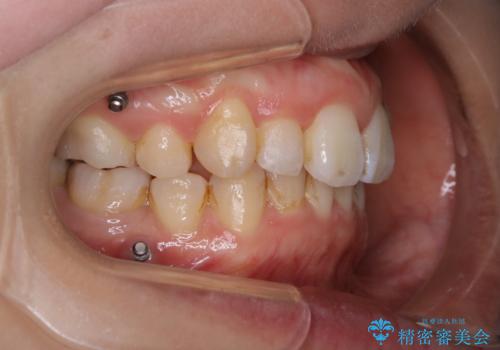

- 全体的に着色が付いているのが気になるとのことで来院されました。

PMTC60分コースを行いました。

着色がかなり頑固なため、エアフローも使い着色を除去していきました。

下の前歯にはかなり多くの歯石が付いており、デンタルフロスでもう少し防げるため、使用法や頻度を確認しました。

インビザラインの矯正治療は、マウスピースの使用時間が少ないとマウスピースと歯のフィッティングが悪くなりシュミレーション通りに歯が動かなくなるため、追加アライナーといって、再度スキャニングを行い新しいフィットの良いマウスピースに変えていきます。そのスキャニング時にアタッチメント(歯の表面に付いた突起)も除去するため、そのタイミングでクリーニングするのもおすすめです。